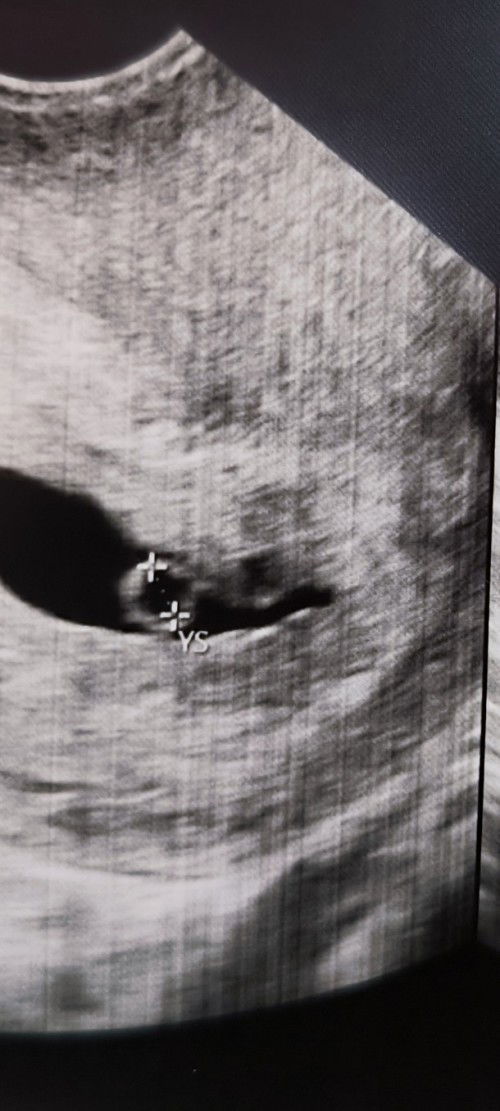

7 weeks preggy. sino po dto naka experience ng mag 1 week ng nag spotting. umiinom nman po ng pampakapit. nag pa emergency n rin sa hospital. ang sabi bed rest at inom lng ng pampakapit. pero ndi p rin na stop ang spotting.. pero okay nman dw si baby. maganda heartbeat nya. pero threaten abortion daw po ako.. super worried na ako, may history n kasi ako ng miscarriage at ectopic.. kaya natatakot ako na mawala p to 😔 #advicepls #pleasehelp

Sa mga naka experience po ng ectopic pregnancy.. ask ko lang po kung surgery lng po ba yung way para matanggal? Currently 6 weeks na po ako. Pero interstitial pregnancy po kasi. 1st pregnancy ko- miscarriage 5weeks 2nd pregnancy- buhay po at sa ngaun 2 y/o n sya via cs. 3rd pregnancy- ito pong pag bubuntis ko ngaun ectopic po. Salamat sa saaagot#advicepls #pleasehelp #pregnancy